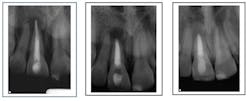

Missed canal anatomy cases ...

Separated instrument with incomplete fill and debridement